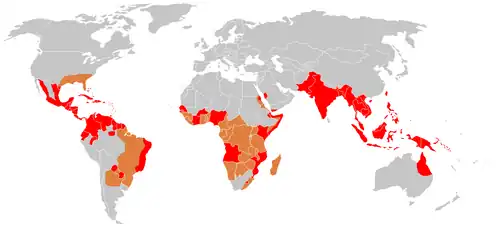

O tratamento da dengue é de apoio, com reidratação oral ou intravenosa para os casos leves ou moderados e fluidos intravenosos e transfusão de sangue para os casos mais graves. O número de casos da doença tem aumentado dramaticamente desde os anos 1960, com cerca de 50 a 390 milhões de pessoas infectadas todos os anos. A dengue é endêmica do sudeste asiático e as primeiras descrições da doença datam de 1779, sendo que sua causa viral e seu modo de transmissão foram descobertos no início do século XX. A dengue tornou-se um problema global desde a Segunda Guerra Mundial e é endêmica em mais de 110 países diferentes, principalmente em regiões tropicais de Oceania, África Oriental, Caribe e América. Além de eliminar os mosquitos, pesquisas para o desenvolvimento de uma vacina contra a dengue e medicação diretamente orientada para esse tipo de vírus são formas de controlar a doenças.[4]